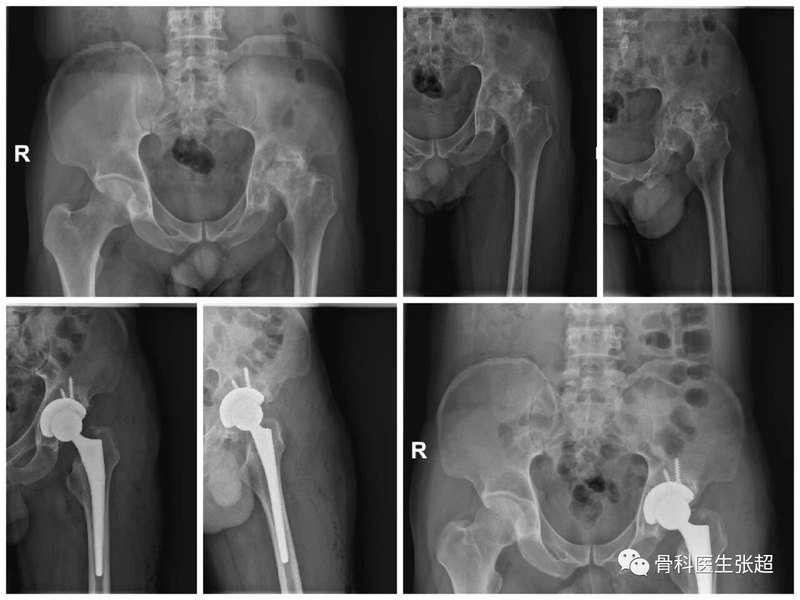

股骨頭壞死、髖關(guān)節(jié)骨性關(guān)節(jié)炎以髖關(guān)節(jié)類風(fēng)濕性關(guān)節(jié)炎人工髖關(guān)節(jié)置換手術(shù)治療。以往的人工髖關(guān)節(jié)是通過后方入路來完成,手術(shù)創(chuàng)傷大,需要切斷肌肉肌腱來顯露髖關(guān)節(jié),從而完成髖關(guān)節(jié)假體的安裝。術(shù)后需要更長的時間來康復(fù)。直接前方入路(DAA)微創(chuàng)髖關(guān)節(jié)置換手術(shù)是通過髖關(guān)節(jié)前方的肌肉間隙顯露髖關(guān)節(jié),創(chuàng)傷小,軟組織損傷小,術(shù)后恢復(fù)快。DAA入路目前是美國比較常用的髖關(guān)節(jié)置換手術(shù)入路。我科目前常規(guī)開展DAA微創(chuàng)髖關(guān)節(jié)置換手術(shù),讓患者受益,得到患者及家屬的認可的好評。近日為一位受股骨頭壞死困擾多的患者進行了全髖關(guān)節(jié)置換手術(shù),術(shù)后12小時,患者在復(fù)查X光片就下地行走,患者自覺切口不痛,行走時髖部疼痛較手術(shù)前明顯減輕,關(guān)節(jié)靈活程度明顯改善。圖片左側(cè)股骨頭壞死并關(guān)節(jié)炎,行左側(cè)全髖置換手術(shù)。門診時間云南省第一人民醫(yī)院。周一上午門診,2號門診3樓外科診區(qū)4診室;周六上午2號門診3樓外科診區(qū)